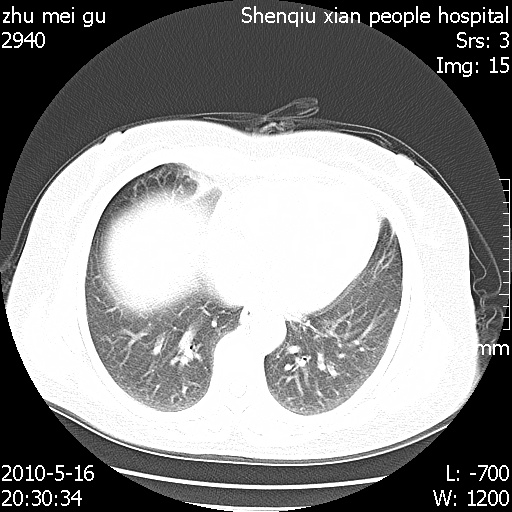

标题: CT26733:能否诊断支扩?

患者,女,62岁,有反复咯血史10年,近三年来大咯血数次,每次量在500-1000ml

图像不全。右中叶内侧段陈旧性病灶。

支持:图像不全。右中叶内侧段纤维、钙化灶。

右中叶内侧段慢性感染性病变,不排除合并支气管扩张可能。

右中叶内侧段纤维、钙化灶.

支持轻度纤维化,不支持支气管扩张。

建议hrct